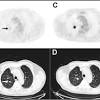

How To Detect Lung Cancer Ct Scan : Serial Chest Ct Scans A At The Time Of The Small Cell Lung Cancer Download Scientific Diagram / This provides a series of images from many different angles.. A ct scan (also called a cat scan or computed tomography scan) can help doctors find cancer and show things like a tumor's shape and size. This lung cancer awareness month learn how future processing is able to detect lung cancer from ct scans with the help of ai. The computer puts them together to make a 3 dimensional (3d) image. How does a ct or cat scan work? It can also show the size, shape, and position of any lung tumors and can help find enlarged lymph nodes that might contain cancer that has spread.

Ct screening for lung cancer has only been studied in people at high risk of lung cancer — those with a long smoking history and who are 55 and older. Because ct scans can detect even very small nodules in the lungs, ldct of the chest is especially effective for diagnosing lung cancer at its earliest, most health insurance companies and medicare will only cover the cost of an ldct scan to screen for lung cancer in patients who meet certain criteria. A ct scan can help to diagnose lung cancer. Lung cancer is the world's deadliest cancer and it takes countless lives each year. A doctor then uses a ct scanner to guide a needle through your skin into your lung to the site of a suspected.

It's also important to follow recommended screening guidelines, which can help detect certain cancers early. Ct (or cat) stands for computed (axial) tomography. Pet and nuclear medicine scans. What to expect when undergoing this test. Low dose ct scan (low dose computed tomography scan). Abstract—lung nodules are potential manifestations of lung cancer, and their early detection facilitates early treatment and improves patient's for this reason, cad systems for lung cancer have been proposed in several studies. Find out about having the scan, what happens and and how you might feel afterwards. Lung cancer screening ct protocols version 5.1 13 september 2019 lung cancer screening. How often should you have a ct scan for lung cancer? The computer puts them together to make a 3 dimensional (3d) image. This provides a series of images from many different angles. It takes pictures from different angles. Ct scans can detect bone and joint problems, like complex bone fractures and tumors.

Learn more about lung cad systems. The computer puts them together to make a 3 dimensional (3d) image. Because ct scans can detect even very small nodules in the lungs, ldct of the chest is especially effective for diagnosing lung cancer at its earliest, most health insurance companies and medicare will only cover the cost of an ldct scan to screen for lung cancer in patients who meet certain criteria. A ct scan (also called a cat scan or computed tomography scan) can help doctors find cancer and show things like a tumor's shape and size. Studies over the last 15 years using early detection screening such as spiral ct have been shown to reduce lung cancer.